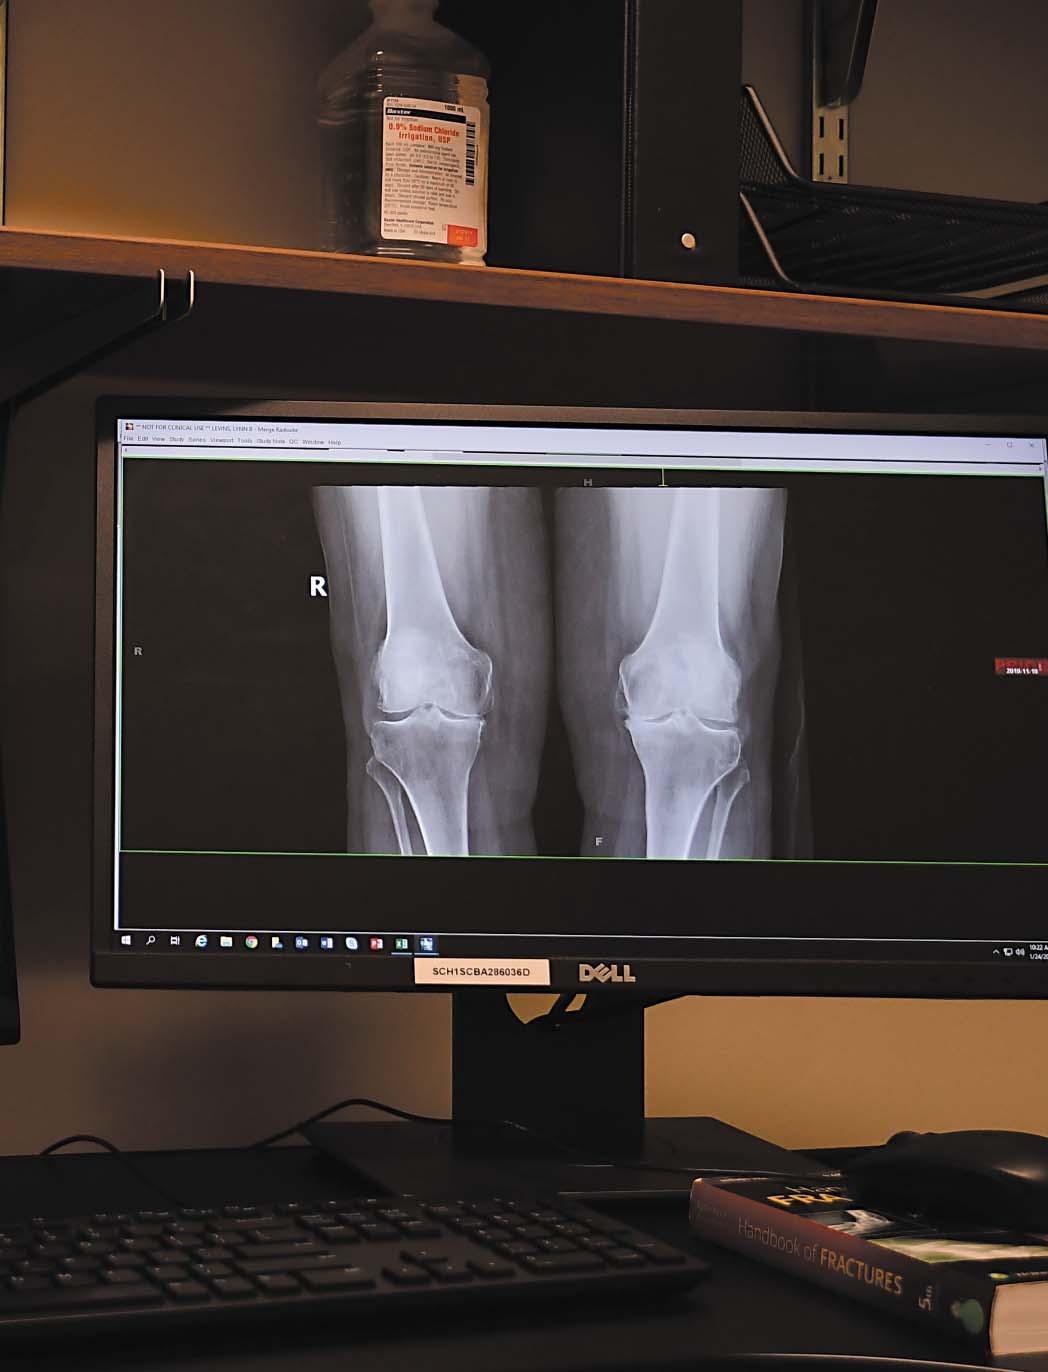

An illustration of a knee implant used in a full replacement surgery and an image of a patient’s knee are displayed on the monitors.

Worthen said using robotic technology makes the surgery more precise with less recovery time required. “The robotic technology gives us an ability to be more exact with some of our steps in the operation in a knee replacement,” Worthen said.